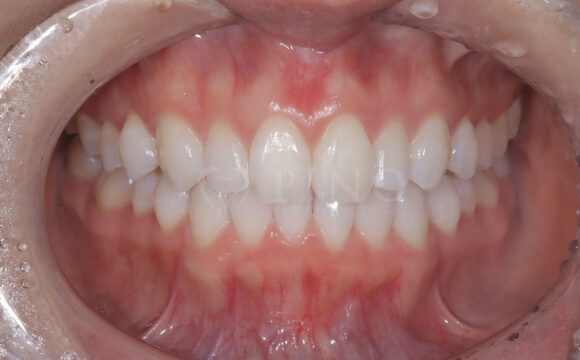

症例12:噛み合わせが深く、下の歯が見えないのが気になる(20代男性)

主訴 噛み合わせが深く、下の歯が見えないのが気になる 診断名 過蓋咬合(かがいこうごう)、顎関節後方転位 治療方法 マウスピース矯正、補綴治療(被せ物、詰め物の治療) 抜歯 なし オルソパルス あり 治療期間 2年 費用 746,000円 + 165,000円(オルソパルス)+ 補綴費用(保険診療) 副作用・注意点 矯正後の後戻りを防ぐためリテーナーの使用が必要となる、詰め物の変色が起こる可能性がある 備考 下顎の位置を正しい位置にするためにスプリントを使用した。ホワイトニングも併用。